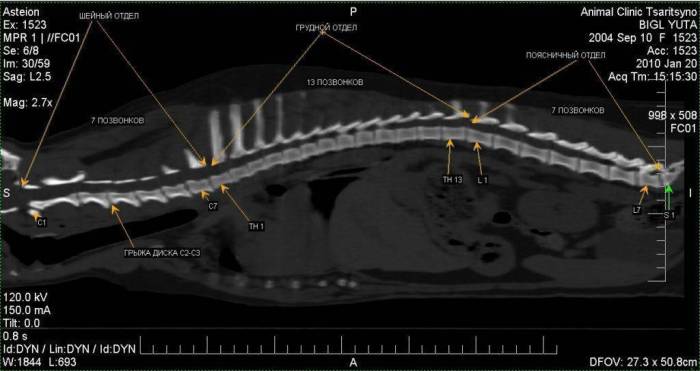

К специальным методам исследования, позволяющим выявить заболевание, относятся рентгенография, миелография, компьютерная (КТ) и магнитно-резонансная томография (МРТ), а в некоторых случаях — миело-КТ.

Наиболее информативными методами диагностики заболеваний межпозвонковых дисков являются МРТ и КТ. Эти исследования отличаются высокой точностью и неинвазивностью.

На компьютерной томографии экструзия межпозвонкового диска будет выглядеть как яркое пятно (ослабленный сигнал). В различных плоскостях на КТ грыжу межпозвонковых дисков можно четко интерпретировать в сагиттальных, аксиальных и коронарных срезах. Это позволяет точно определить длину и расположение грыжи, что предоставляет больше информации для лечения по сравнению с обычной рентгенографией. В некоторых случаях, когда грыжа межпозвонкового диска выглядит как экстрадуральное образование с сильным ослаблением сигнала, например, если содержимое диска смешано с кровью, имеет смысл проводить миело-КТ.